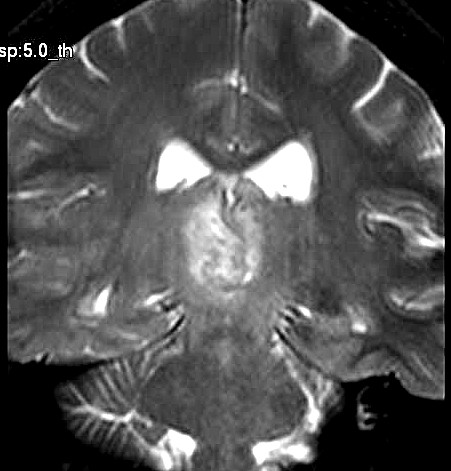

| Fem. 17a. |

| Nódulo sólido homogêneo preenchendo o III ventrículo, com limites precisos, com hipossinal em T1 e hipersinal em T2 e FLAIR, que se impregna por contraste paramagnético. Lesão menor implantada no assoalho do IV ventrículo provavelmente representa disseminação por via liquórica. |

| AXIAIS, FLAIR | T2 | |

| F. 17a. Tumor teratóide rabdóide atípico de III ventrículo. RM | HE | VIM, GFAP | HHF35, desmina, 1A4 | AE1AE3, EMA |